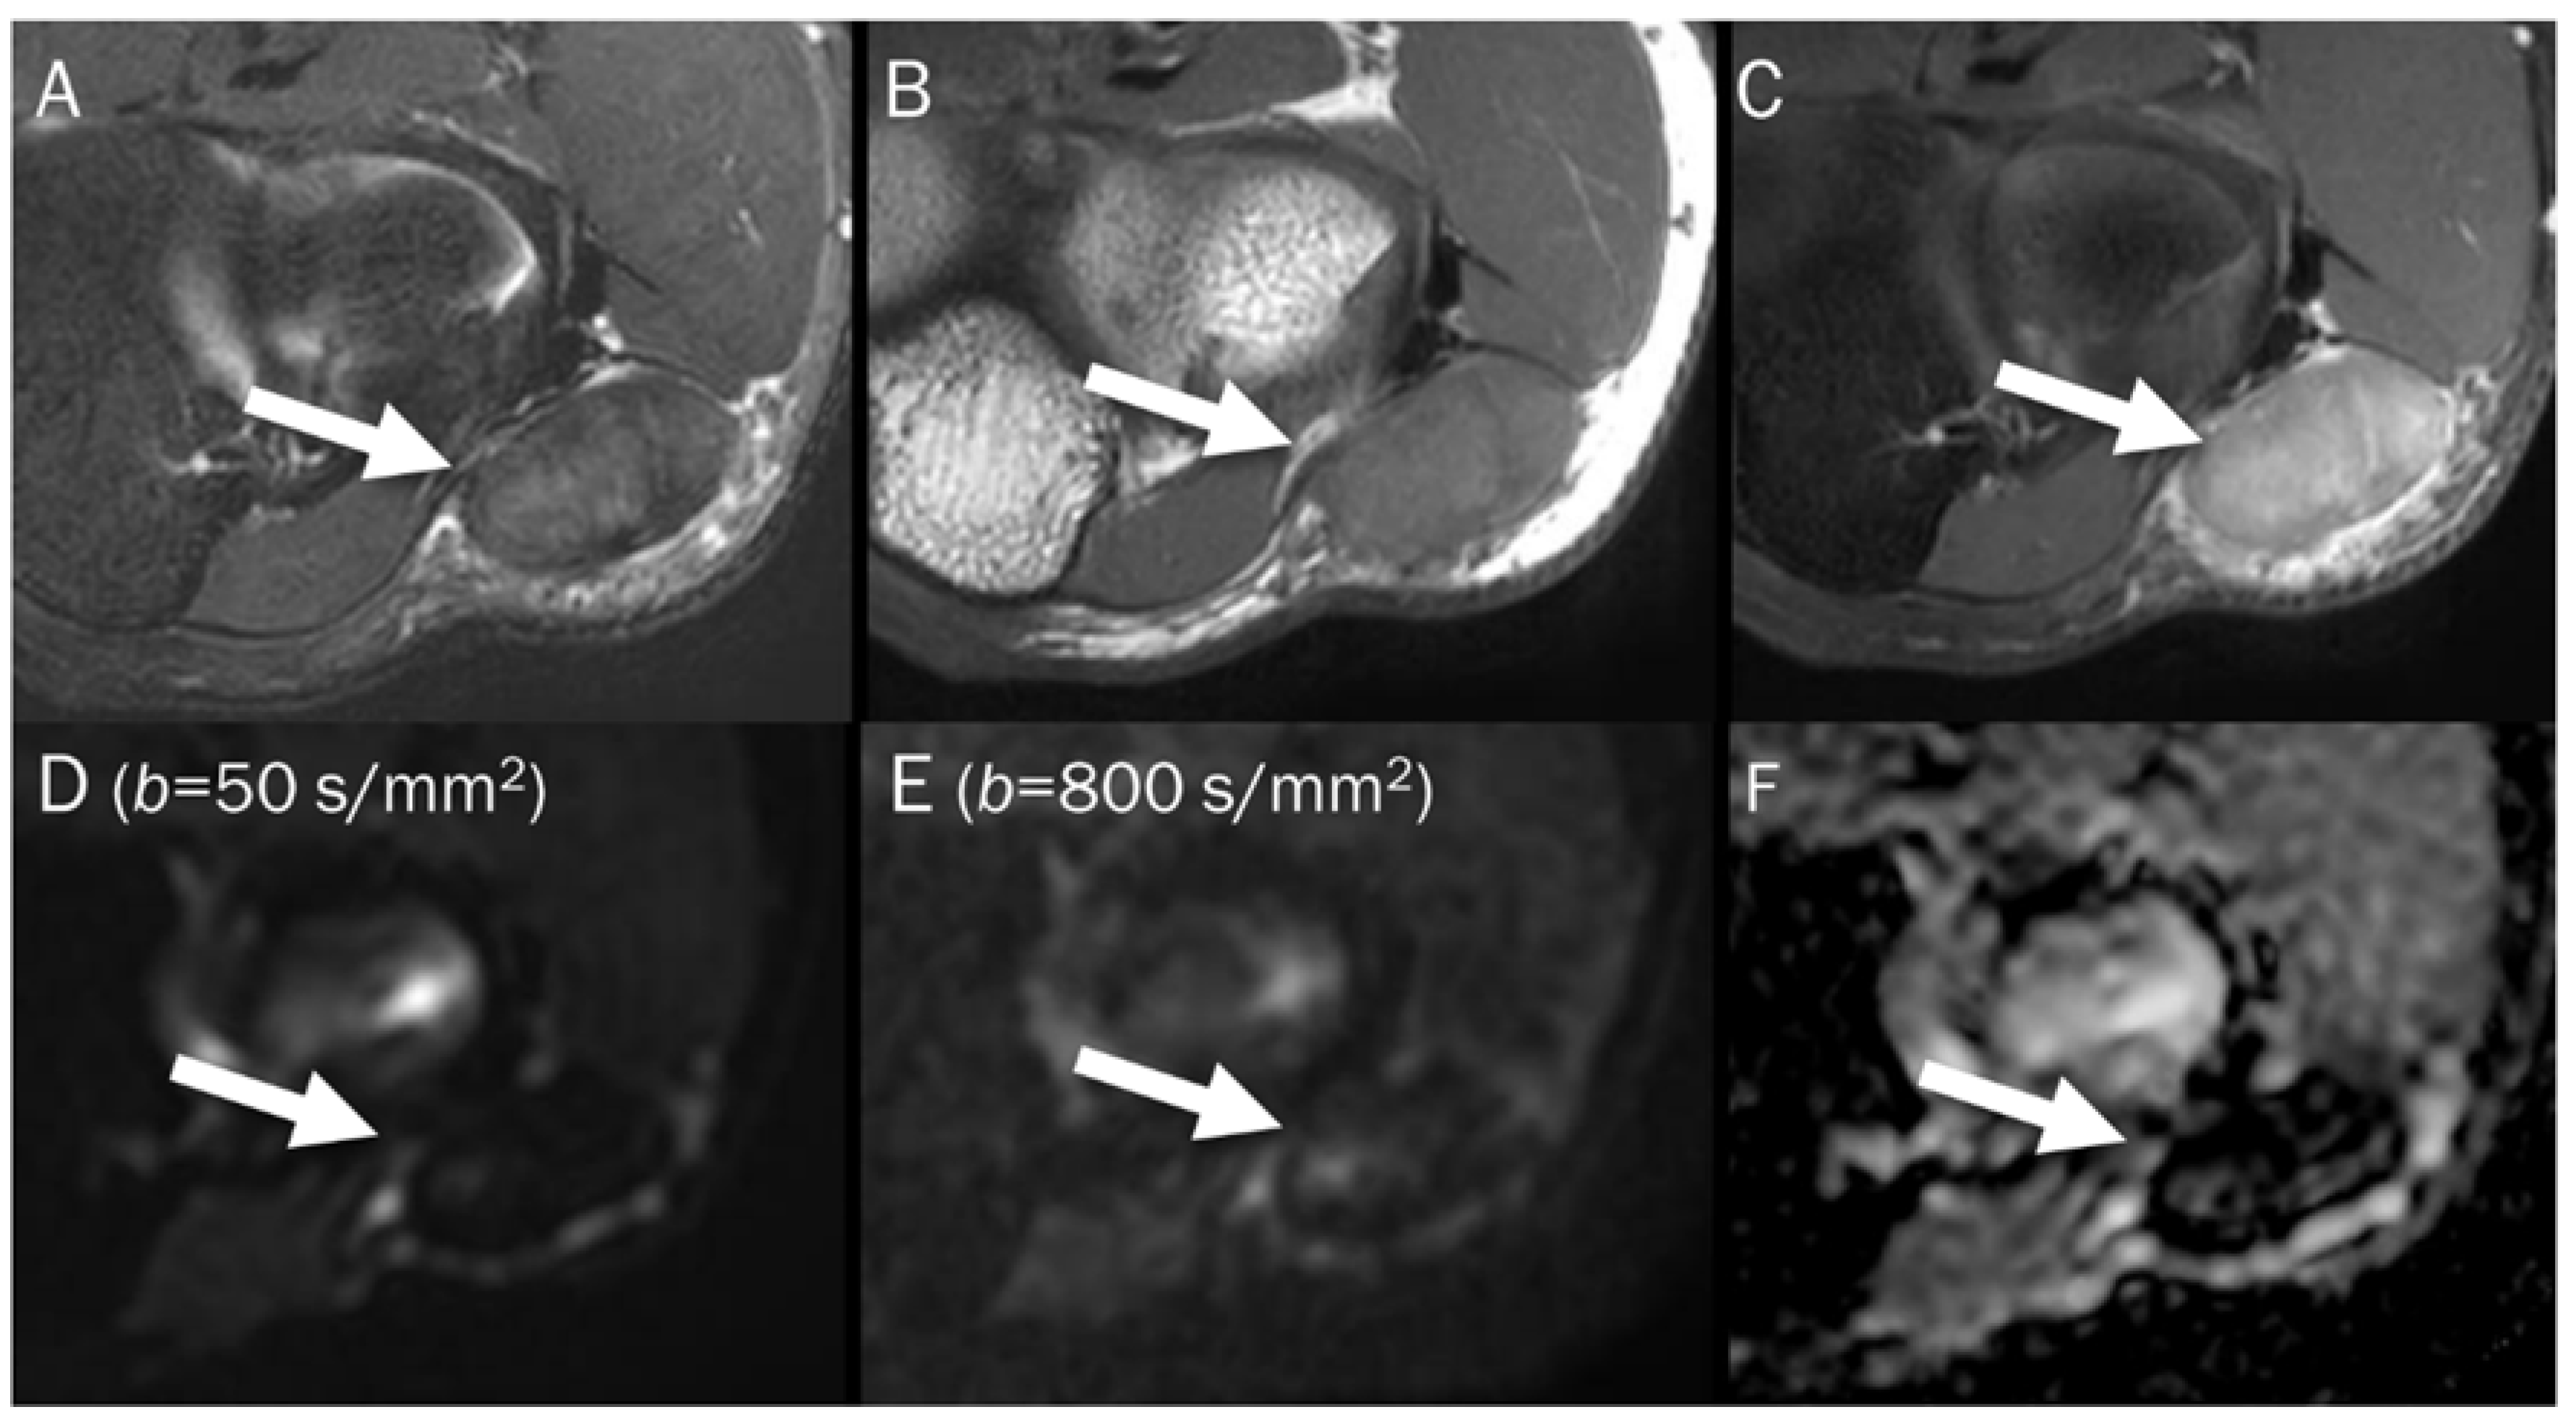

7.2. Hematoma

| Hematoma | ||

| Acute stage | T2 black-out | Deoxyhemoglobin |

| Early subacute stage | T2 black-out | Intracellular methemoglobin |

| Chronic stage | T2 black-out | Hemosiderin |

| Stage | Component | Age | T1WI | T2WI | DWI | ADC Map |

|---|---|---|---|---|---|---|

| Hyperacute | Intracellular oxyhemoglobin | <6 h | Iso | Hyper | Hyper | Hypo |

| Acute | Intracellular deoxyhemoglobin | 6–72 h | Iso | Hypo | Hypo | Hypo |

| Early subacute | Intracellular methemoglobin | 3–7 d | Hyper | Hypo | Hypo | Hypo |

| Late subacute | Extracellular methemoglobin | 1–4 w | Hyper | Hyper | Hyper | Hypo-to-iso |

| Chronic | Hemosiderin | >1 m | Hypo | Hypo | Hypo | Hypo |